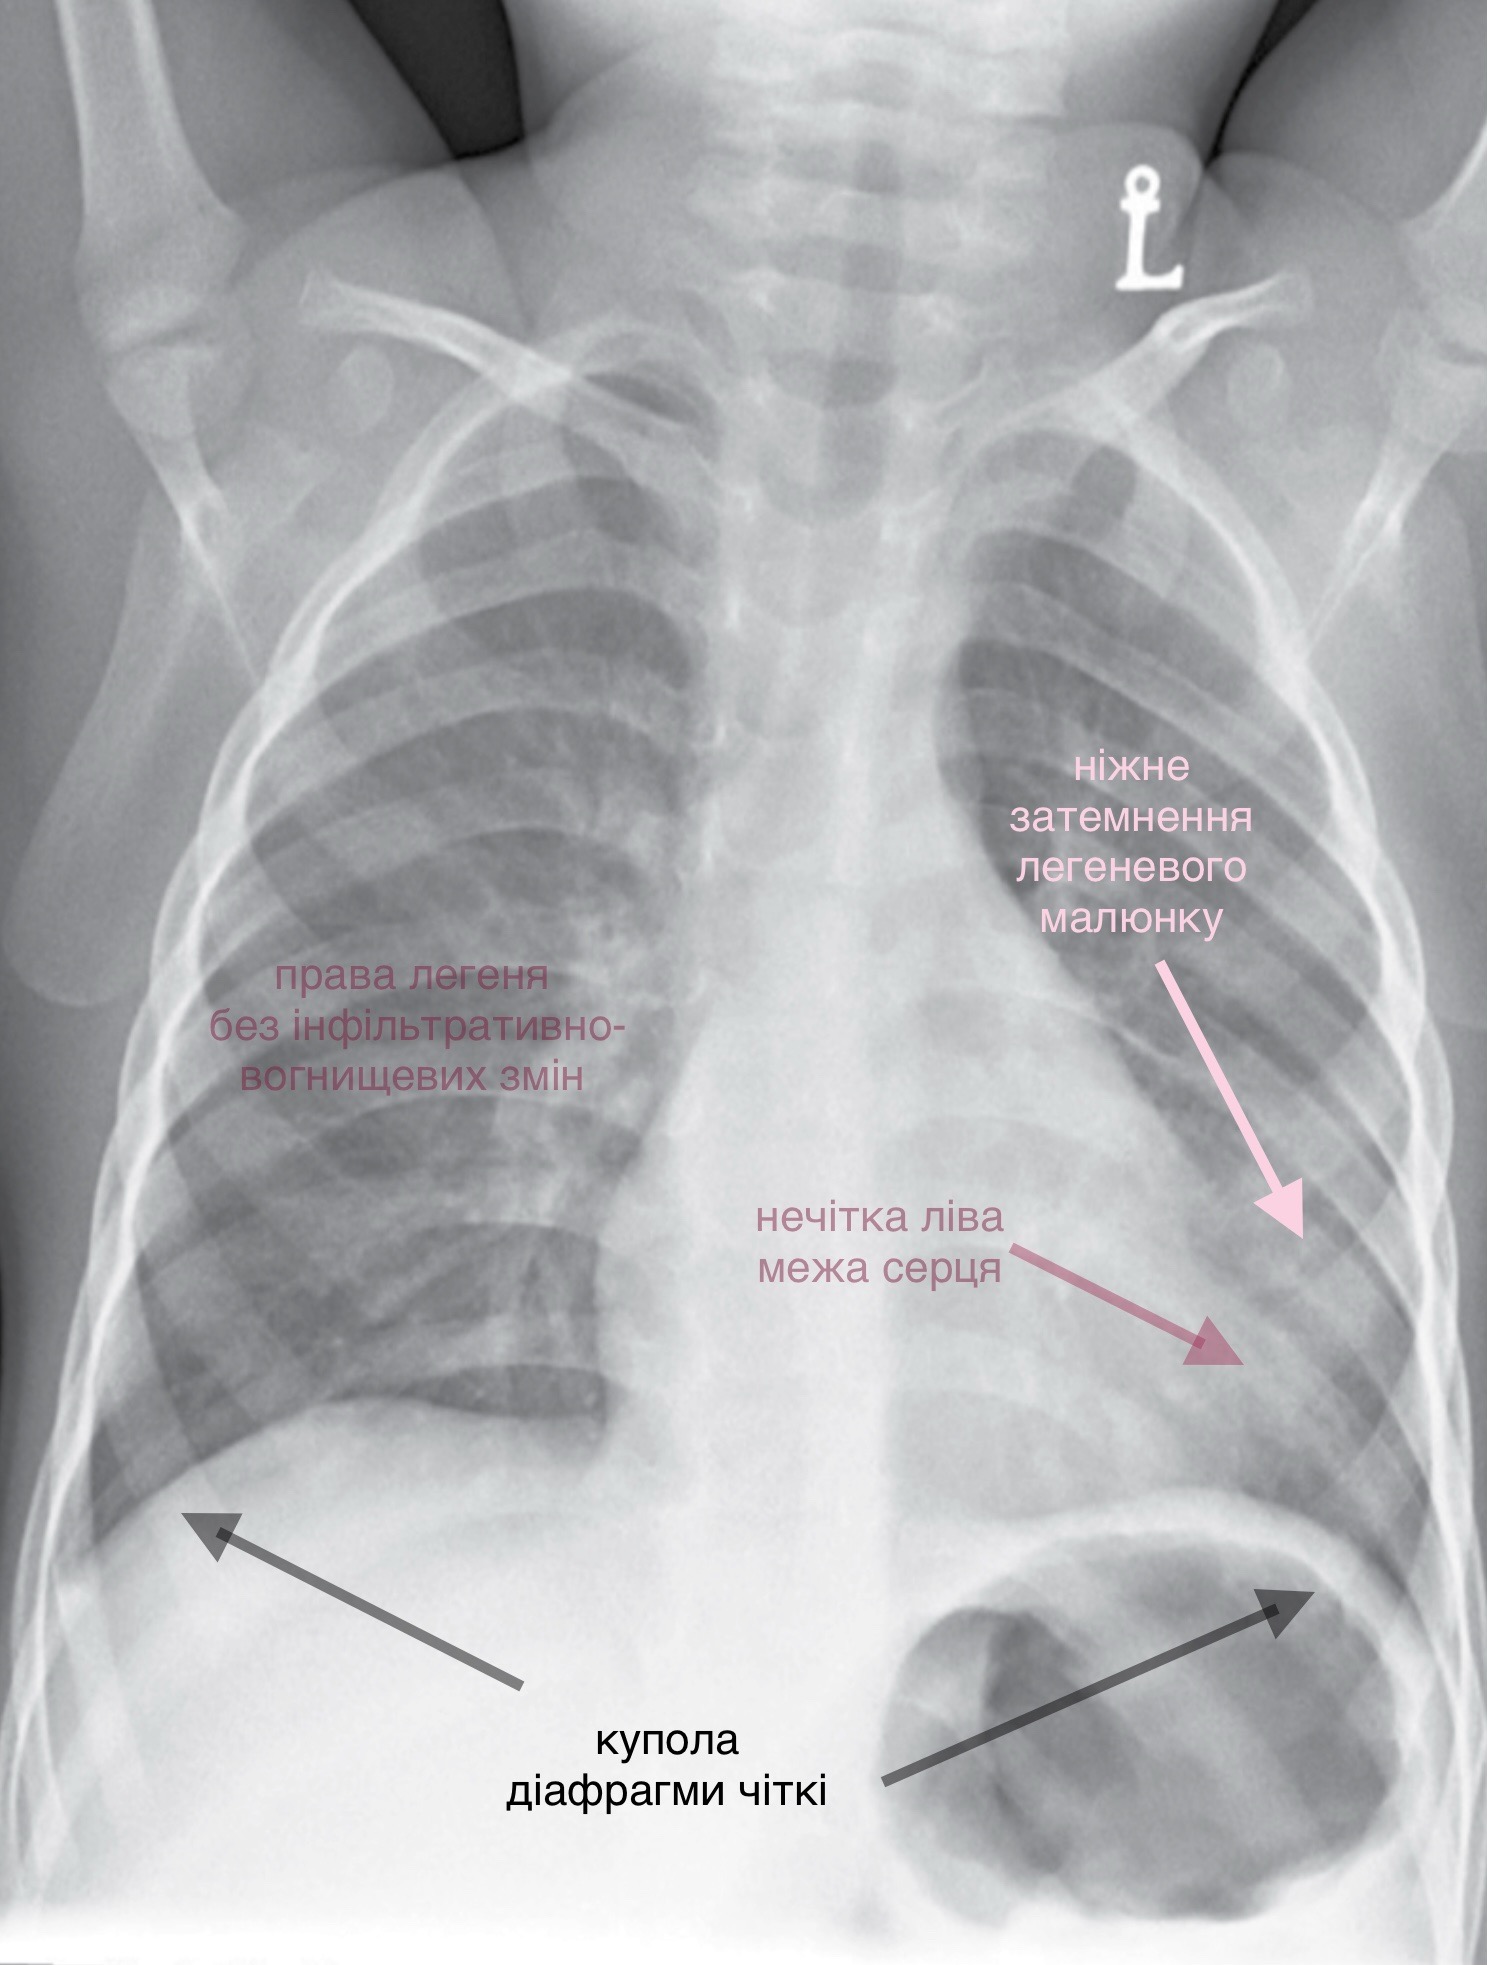

Мати чотирьохрічного хлопчика, який скаржиться на кашель та лихоманку, звернулась до лікарні. При обстеженні температура тіла підвищена, тахіпное. Аускультативно над лівою легенею вислуховуються вологі хрипи.

На дані рентгенограмі ОГК в прямій проекції пацієнт дещо ротований. Відмічається ніжне затемнення у нижніх відділах лівої легені. Ліва межа серця не чітка. Куполи діафрагми чіткі. Права легеня без інфільтративно-вогнищевих змін. Кістково-деструктивні зміни відсутні.

Висновок: на даній рентгенограмі спостерігається лівобічна пневмонія.